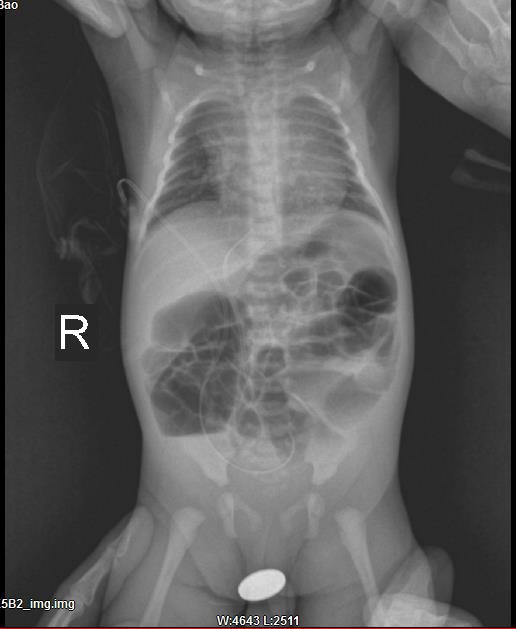

11月15日对于黎大哥一家来说,是一个很特别的日子,全家人兴奋地期盼一个新生命的到来,然后兴奋并没有持续太久,却沉浸在悲伤之中,因为他们的小孩患有先天性畸形疾病—-肛门闭锁伴直肠尿道瘘,即先天没有肛门,粪便只能从与直肠相通的尿道排出。黎大哥一家处于手足无措之中,因为当地医院尚未能开展该类疾病的治疗,在得知我院能开展该疾病的治疗后,家属通过当地医院向我院发来求助,我院连夜派出救护车到200多公里外接回,从小孩出生到进我院...